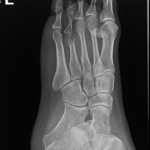

After the desired length has been achieved and the limb has been straightened, no further adjustments are made. The apparatus is left in place to allow the new bone to harden and mature. Once the new bone is judged to be sufficiently strong, the frame is removed under a short general anesthetic. A cast or brace may be applied for an additional month or two for further protection. The new bone tissue assumes all the qualities and strength of normal bone with time.

All the necessary surgeries are anticipated and communicated to the patient before treatment commences but sometimes an unscheduled operation is required to correct a problem. When the desired correction is achieved the frame is locked down and the consolidation phase begins. The patient is seen on a monthly basis with x-rays and examination.

I am very conservative regarding when to remove the frame. This is to minimize the risk of deformation of the regenerate or fracture after frame removal, which can be a devastating complication. When it is thought that it is time to remove the frame then it is completely loosened so that it is not assisting in weight-bearing and the patient is encouraged to fully weight bear for two weeks. If this can be achieved without any loss of correction then the frame removal is scheduled. If there is a loss of position then usually this can be corrected by frame adjustment on an outpatient basis thereby avoiding needing further surgery.